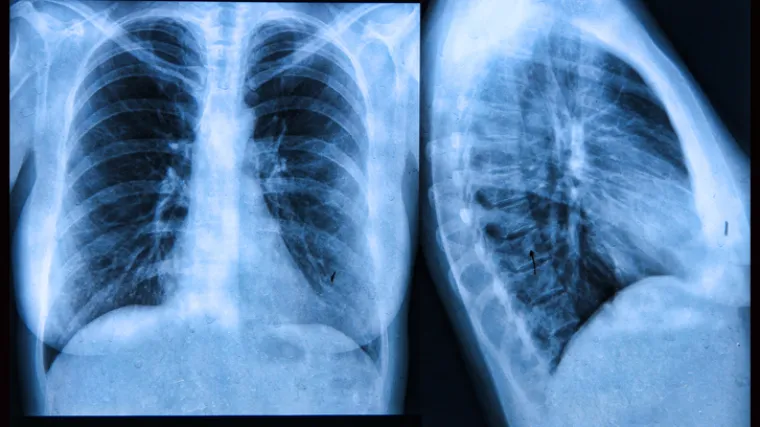

'Rak više nije smrtonosna bolest, sad je kronična, mnogi s time žive'

Na skupu je 120 sudionika, predstavnika 15 zemalja s pet kontinenata. Oni će tijekom tri dana predstaviti modele kako unaprijediti ranu detekciju, prevenciju, liječenje i rehabilitaciju od zloćudnih bolesti, ali i skrenuti pozornost javnosti da dijagnoza raka danas ne znači smrt, rekao je predsjednik kongresa, zagrebački psihijatar Veljko Đorđević.

Cilj je, istaknuo je, stvoriti mrežu sveobuhvatnog pristupa bolesniku jer mnoge stvari još uvijek ne funkcioniraju dobro. Na kongresu će do 25. listopada biti obuhvaćene brojne teme, od zdravstvene promocije i prevencije, preko različitih modaliteta liječenja, suportivne onkologije, palijativne medicine, psihoonkologije, komunikacijskih vještina u onkologiji, umjetnosti i onkologije, do zdravstvenih politika i rada udruga pacijenata.

Kao cilj zdravstvene politike na kongresu je istaknuto smanjenje čimbenika rizika u idućih 10 godina i promjena načina života, a poseban naglasak stavljen je na pušenje, prekomjernu tjelesnu težinu i fizičku neaktivnost, po čemu je, istaknuo je hrvatski onkolog Eduard Vrdoljak, Hrvatska u samom europskom vrhu.